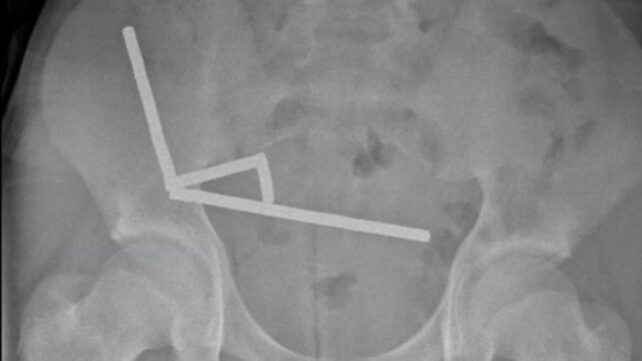

X-rays revealed a shocking sight: four linear chains of tiny neodymium magnets measuring just 5×2 millimeters each, lodged in separate sections of his bowel. These rare earth magnets, which are up to 50 times stronger than regular refrigerator magnets, had attracted each other through different parts of the digestive tract.

Case Images